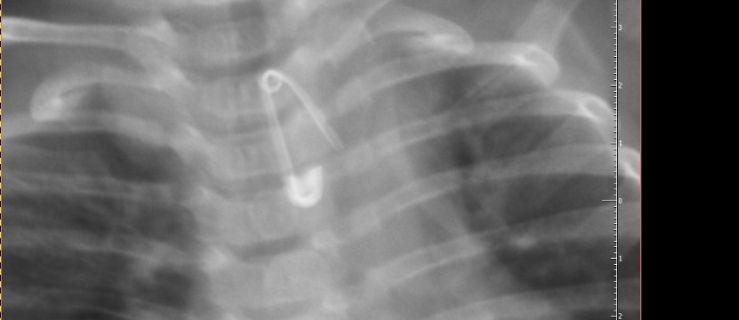

Rodzice z 6-miesięcznym Kubusiem natychmiast wsiedli w samochód i pojechali do szpitala w Krotoszynie. I choć - jak wykazało zdjęcie rentgenowskie - malec połknął 2-centymetrową agrafkę, która, rozwarta, skierowana była ostrzem w dół w przełyku chłopca - lekarka pełniąca dyżur w Szpitalnym Oddziale Ratunkowym w Krotoszynie kazała rodzicom zawieźć chłopca do szpitala w Ostrowie Wlkp. Chociaż w tym czasie na stanie były dwie karetki kazała im jechać własnym samochodem.

Na miejscu wykonano badanie RTG przełyku i jamy brzusznej, które potwierdziło obecność w przełyku ciała obcego. Po wykonaniu tego badania, pełniąca wówczas dyżur oskarżona lekarka, nie wykonując dalszej diagnostyki i nie zapoznając się z dokumentacją medyczną chłopca poleciła rodzicom przetransportowanie chłopca do Szpitala w Ostrowie Wielkopolskim ich prywatnym samochodem – tłumaczy Krzysztof Bukowiecki, rzecznik prasowy prokuratury regionalnej w Łodzi.